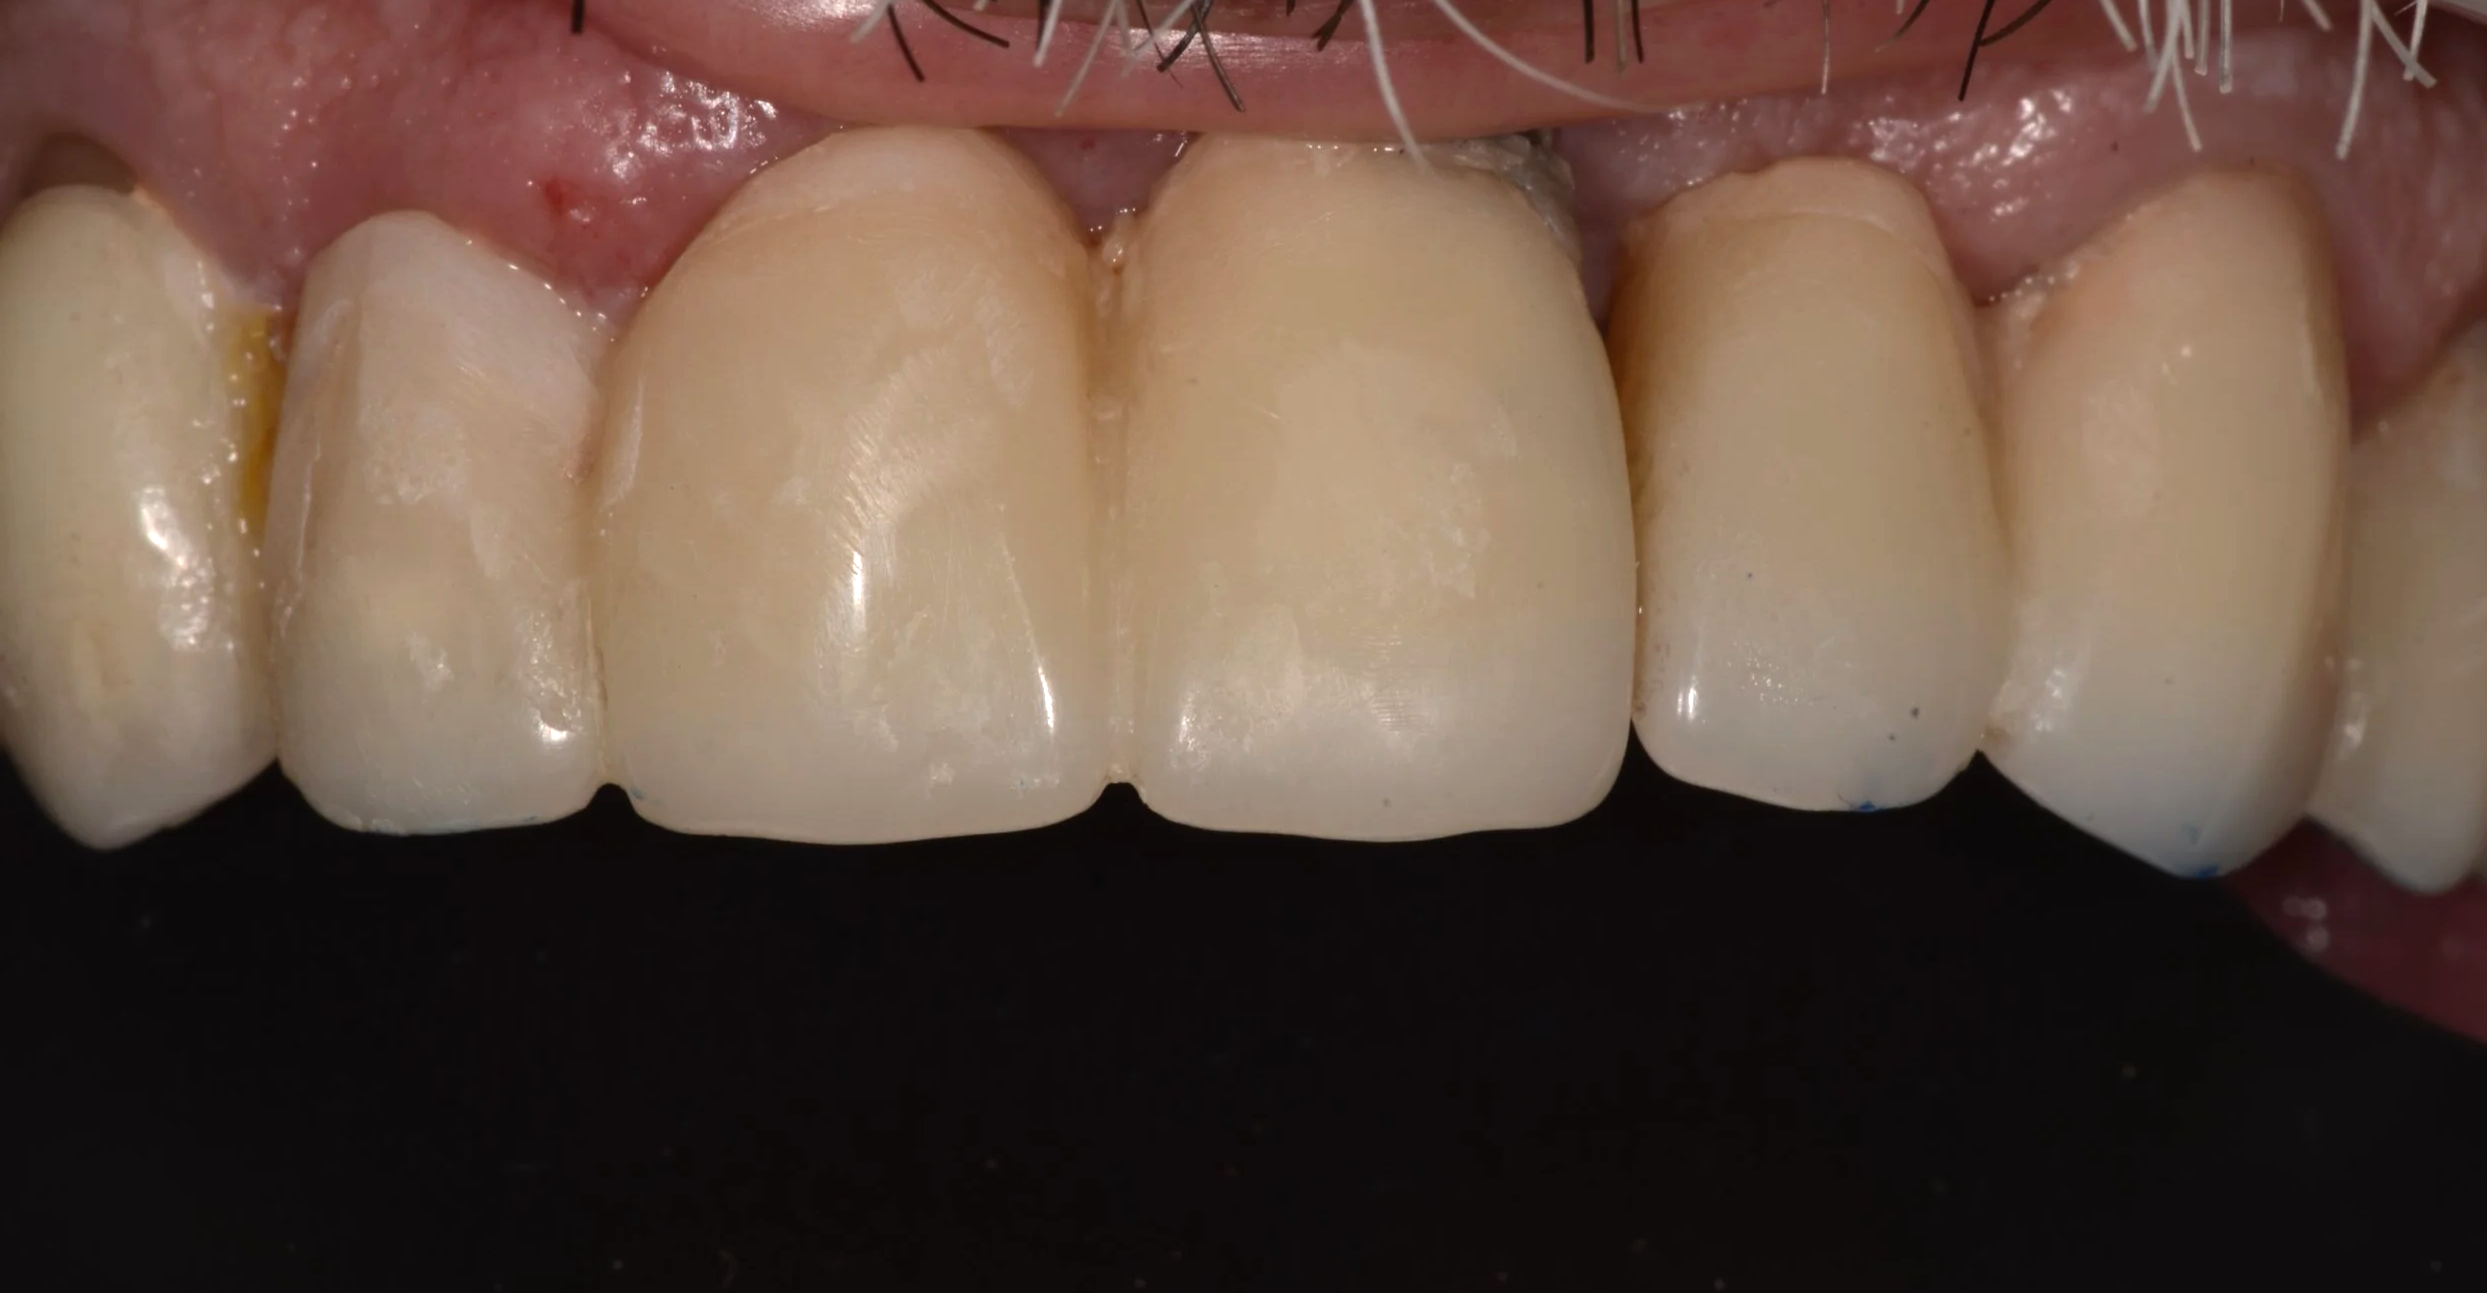

RESULTADO FINAL: El paciente quedó conforme con el tratamiento, recuperó su salud, confort y estética.

Después